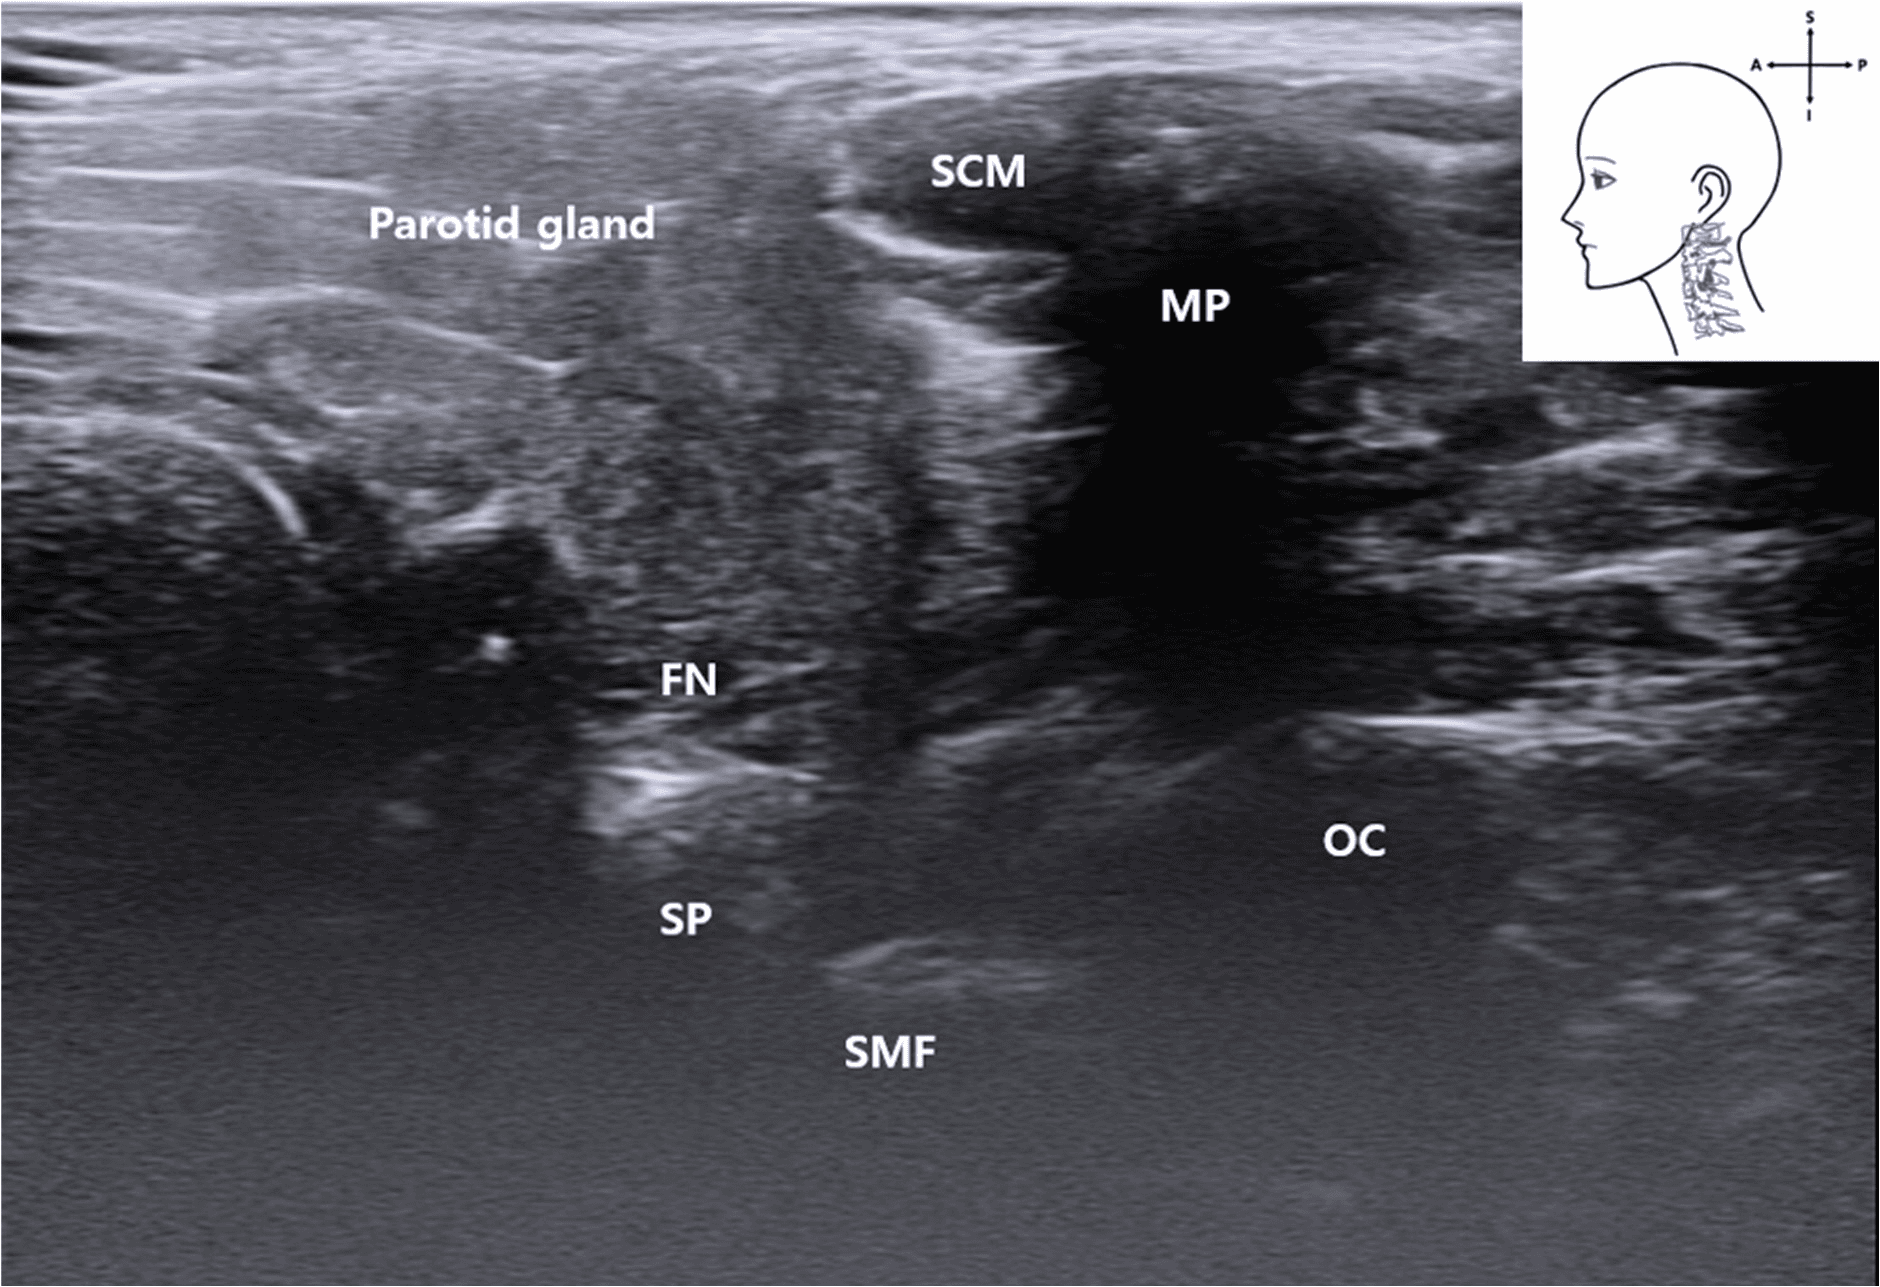

안면마비 - Ultrasound image showing the FN emerging between the mastoid and SP. The styloma Figure 9. Ultrasound image showing the FN emerging between the mastoid and SP. The stylomastoid foramen is not directly visualized as a discrete opening but inferred from the acoustic shadowing pattern between the bony landmarks. MP , mastoid process; PBDM , posterior belly of digastric muscle; FN , facial nerve; SP , styloid process; OC , occipital condyle; SCM , sternocleidomastoid muscle; SMF , stylomatoid foramen); blue rectangle, probe position.